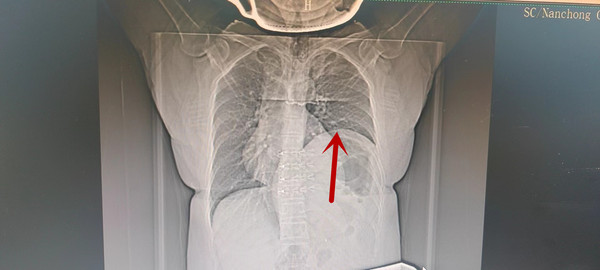

小儿膈膨升 - 好大夫在线

图片尺寸3264x2448